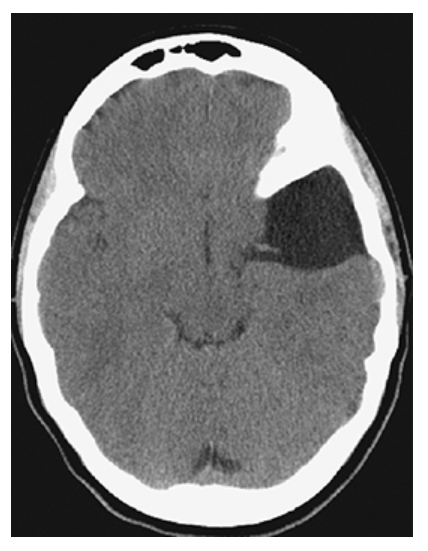

Hydrocephalus. Axial NECT shows markedly dilated lateral ventricles.